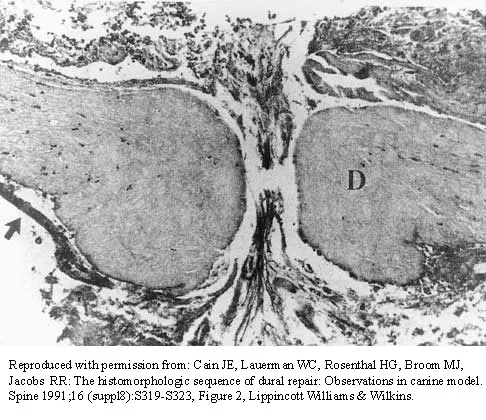

The photomicrograph in Figure 37 shows a repaired dural tear 4 days after surgery. The material interposed between the dural edges (D) is composed of